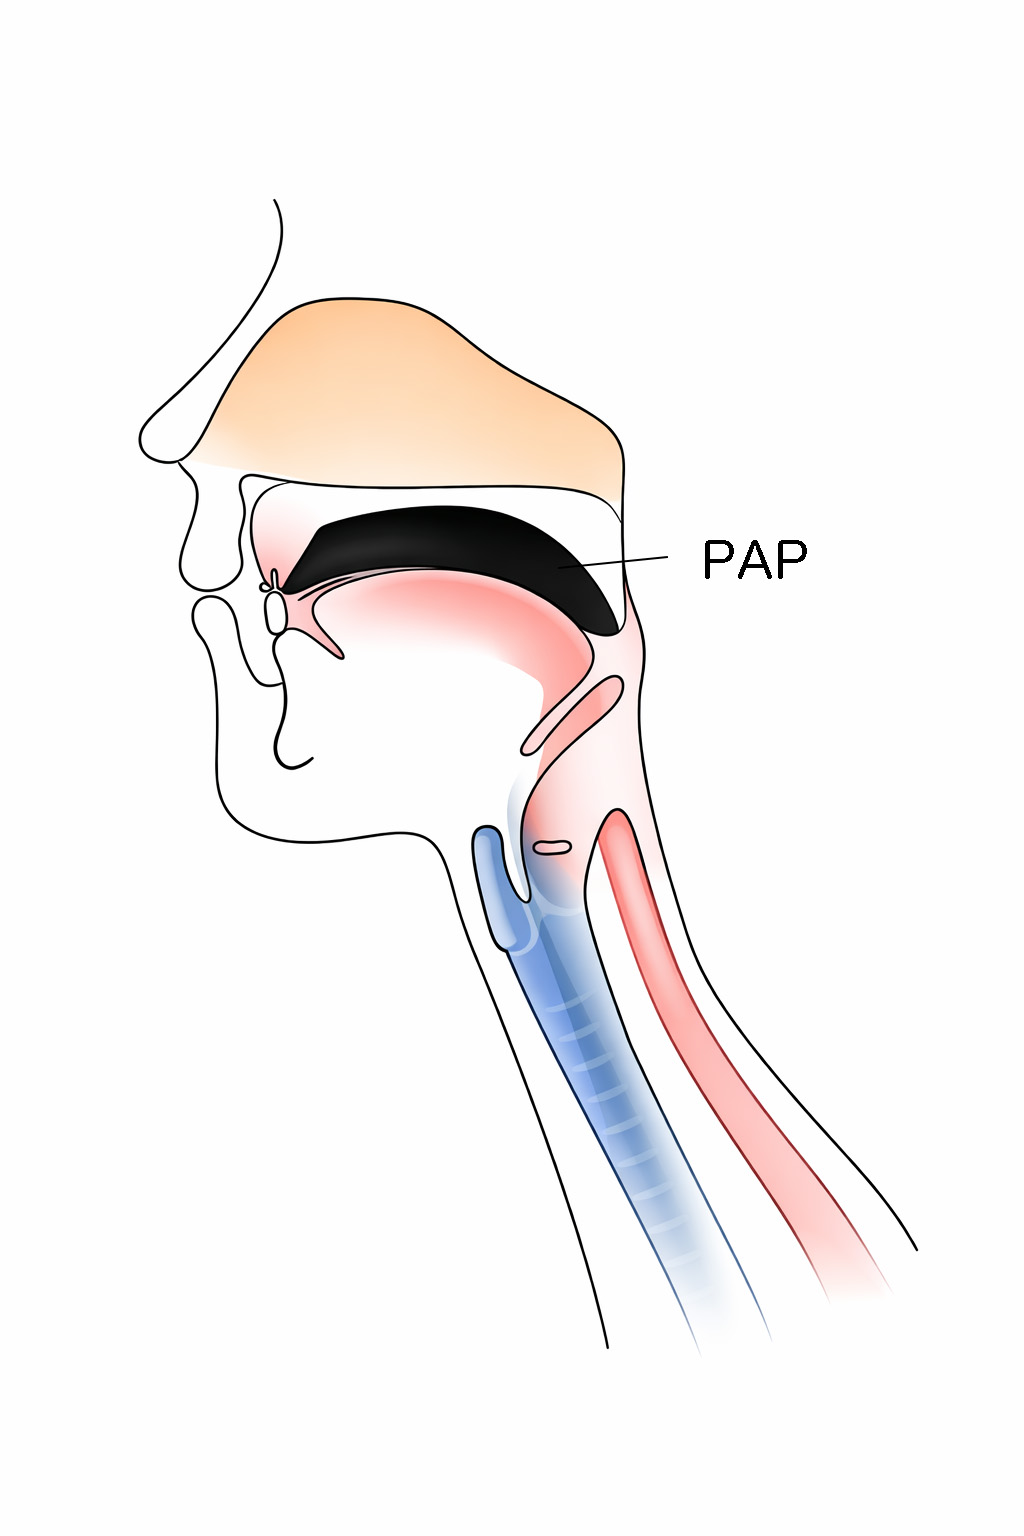

舌接触補助床(PAP)とは,手術やけがなどで舌(した)の一部がなくなった方や,脳梗塞などの病気で舌の動きが弱くなってご飯が食べられない方や,うまく言葉を話せない方のために作る,舌の動きを助けるための特別な入れ歯の一種です.上あごの入れ歯や装置の一部の厚みを増やすことで,舌と上あごの接触を良くし,咀嚼(そしゃく)や飲み込み,発音などのお口の機能の改善を図る装置です.

舌接触補助床が適用される患者さんは,主に舌や下あごの腫瘍などによって舌の一部や全てなくなった方や,脳梗塞やパーキンソン病などの飲み込みや発音に障害がみられた方になります.また,このような病歴がない方でも,舌の筋力測定(舌圧検査)で一定の基準を満たさなかった方も適用されることがあります.

舌は,食べ物を噛んで飲み込むときや,言葉を発音するときに大切な役割を担っています.しかし,舌の一部を失ったり,動きが制限されると,

・食べ物をうまくまとめられず,飲み込めない

・「サ」「タ」「ナ」「ラ」などの音が発音しにくい

・舌が上顎に届かず,言葉がはっきりしない

といった不自由が生じます.

舌接触補助床は,失われた舌の高さや届く範囲を入れ歯や装置の“厚み”を増やしたり調整したりすることで,舌が上あごに接触しやすくなるようにサポートすることで,食事や会話をより自然に行えるようにします.

舌接触補助床を装着することで,以下の機能改善が期待されます.

①食べ物をまとめやすくなり,飲み込みがスムーズになる

②言葉が明瞭になり,会話がしやすくなる

③舌の動きが自然になり,発音のストレスが減る

ただし,会話と飲み込みの際の舌の動きは異なるため,両方の機能を同時に改善することができないことがあります.その際は,食事用と会話用の2種類の舌接触補助床を製作することがあります.補綴の分野でとても大切な役割を担っています。